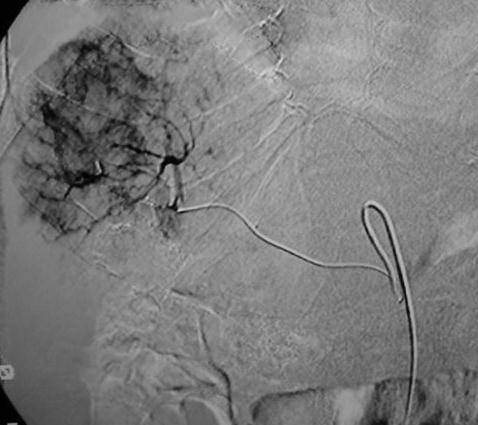

当肿瘤比较局限,导管可以前进至段或者亚段动脉,从而只对存在肿瘤区域进行化学栓塞。使用这项技术时推荐使用共轴的微导管。整体肿瘤区域是否完全被导管栓塞可以从动脉造影中估计,但是,从导管内注入造影剂时进行动脉造影CT可以得到更准确的评价。

碘化油的量取决于肿瘤的大小和血管分布,导管置入部位,和肝功能受损情况。一般剂量为3至10毫升。在靶动脉内放置的导管内注射2%的利多卡因5ml后再进行化学栓塞注射。这样可以避免在操作过程中或操作刚结束时肝脏内产生的剧烈疼痛。然后,抗肿瘤药物与碘化油的混合物被缓慢注入。最后,被剪成小块状的明胶海绵或海绵颗粒或PVA与造影剂和少量的抗肿瘤药物的混合物注入肝动脉。如果存在肝外侧支动脉,则在此动脉中也应放置导管,进行化学栓塞。如果存在显著的动-门脉短路,则在注入碘化油乳剂前,应首先注入少量明胶海绵以阻断血流。动-肝静脉短路也应该被同样处理,但在注入碘化油之前寻找是否有到体循环的短路是最重要的,避免肝动脉栓塞后的肺栓塞。 注入碘化油乳剂之后,应进行数字减影血管造影(DSA),从而确定肿瘤染色是否已经消失。术后定期应拍摄腹部X线片,以确定碘化油是否持续沉积。